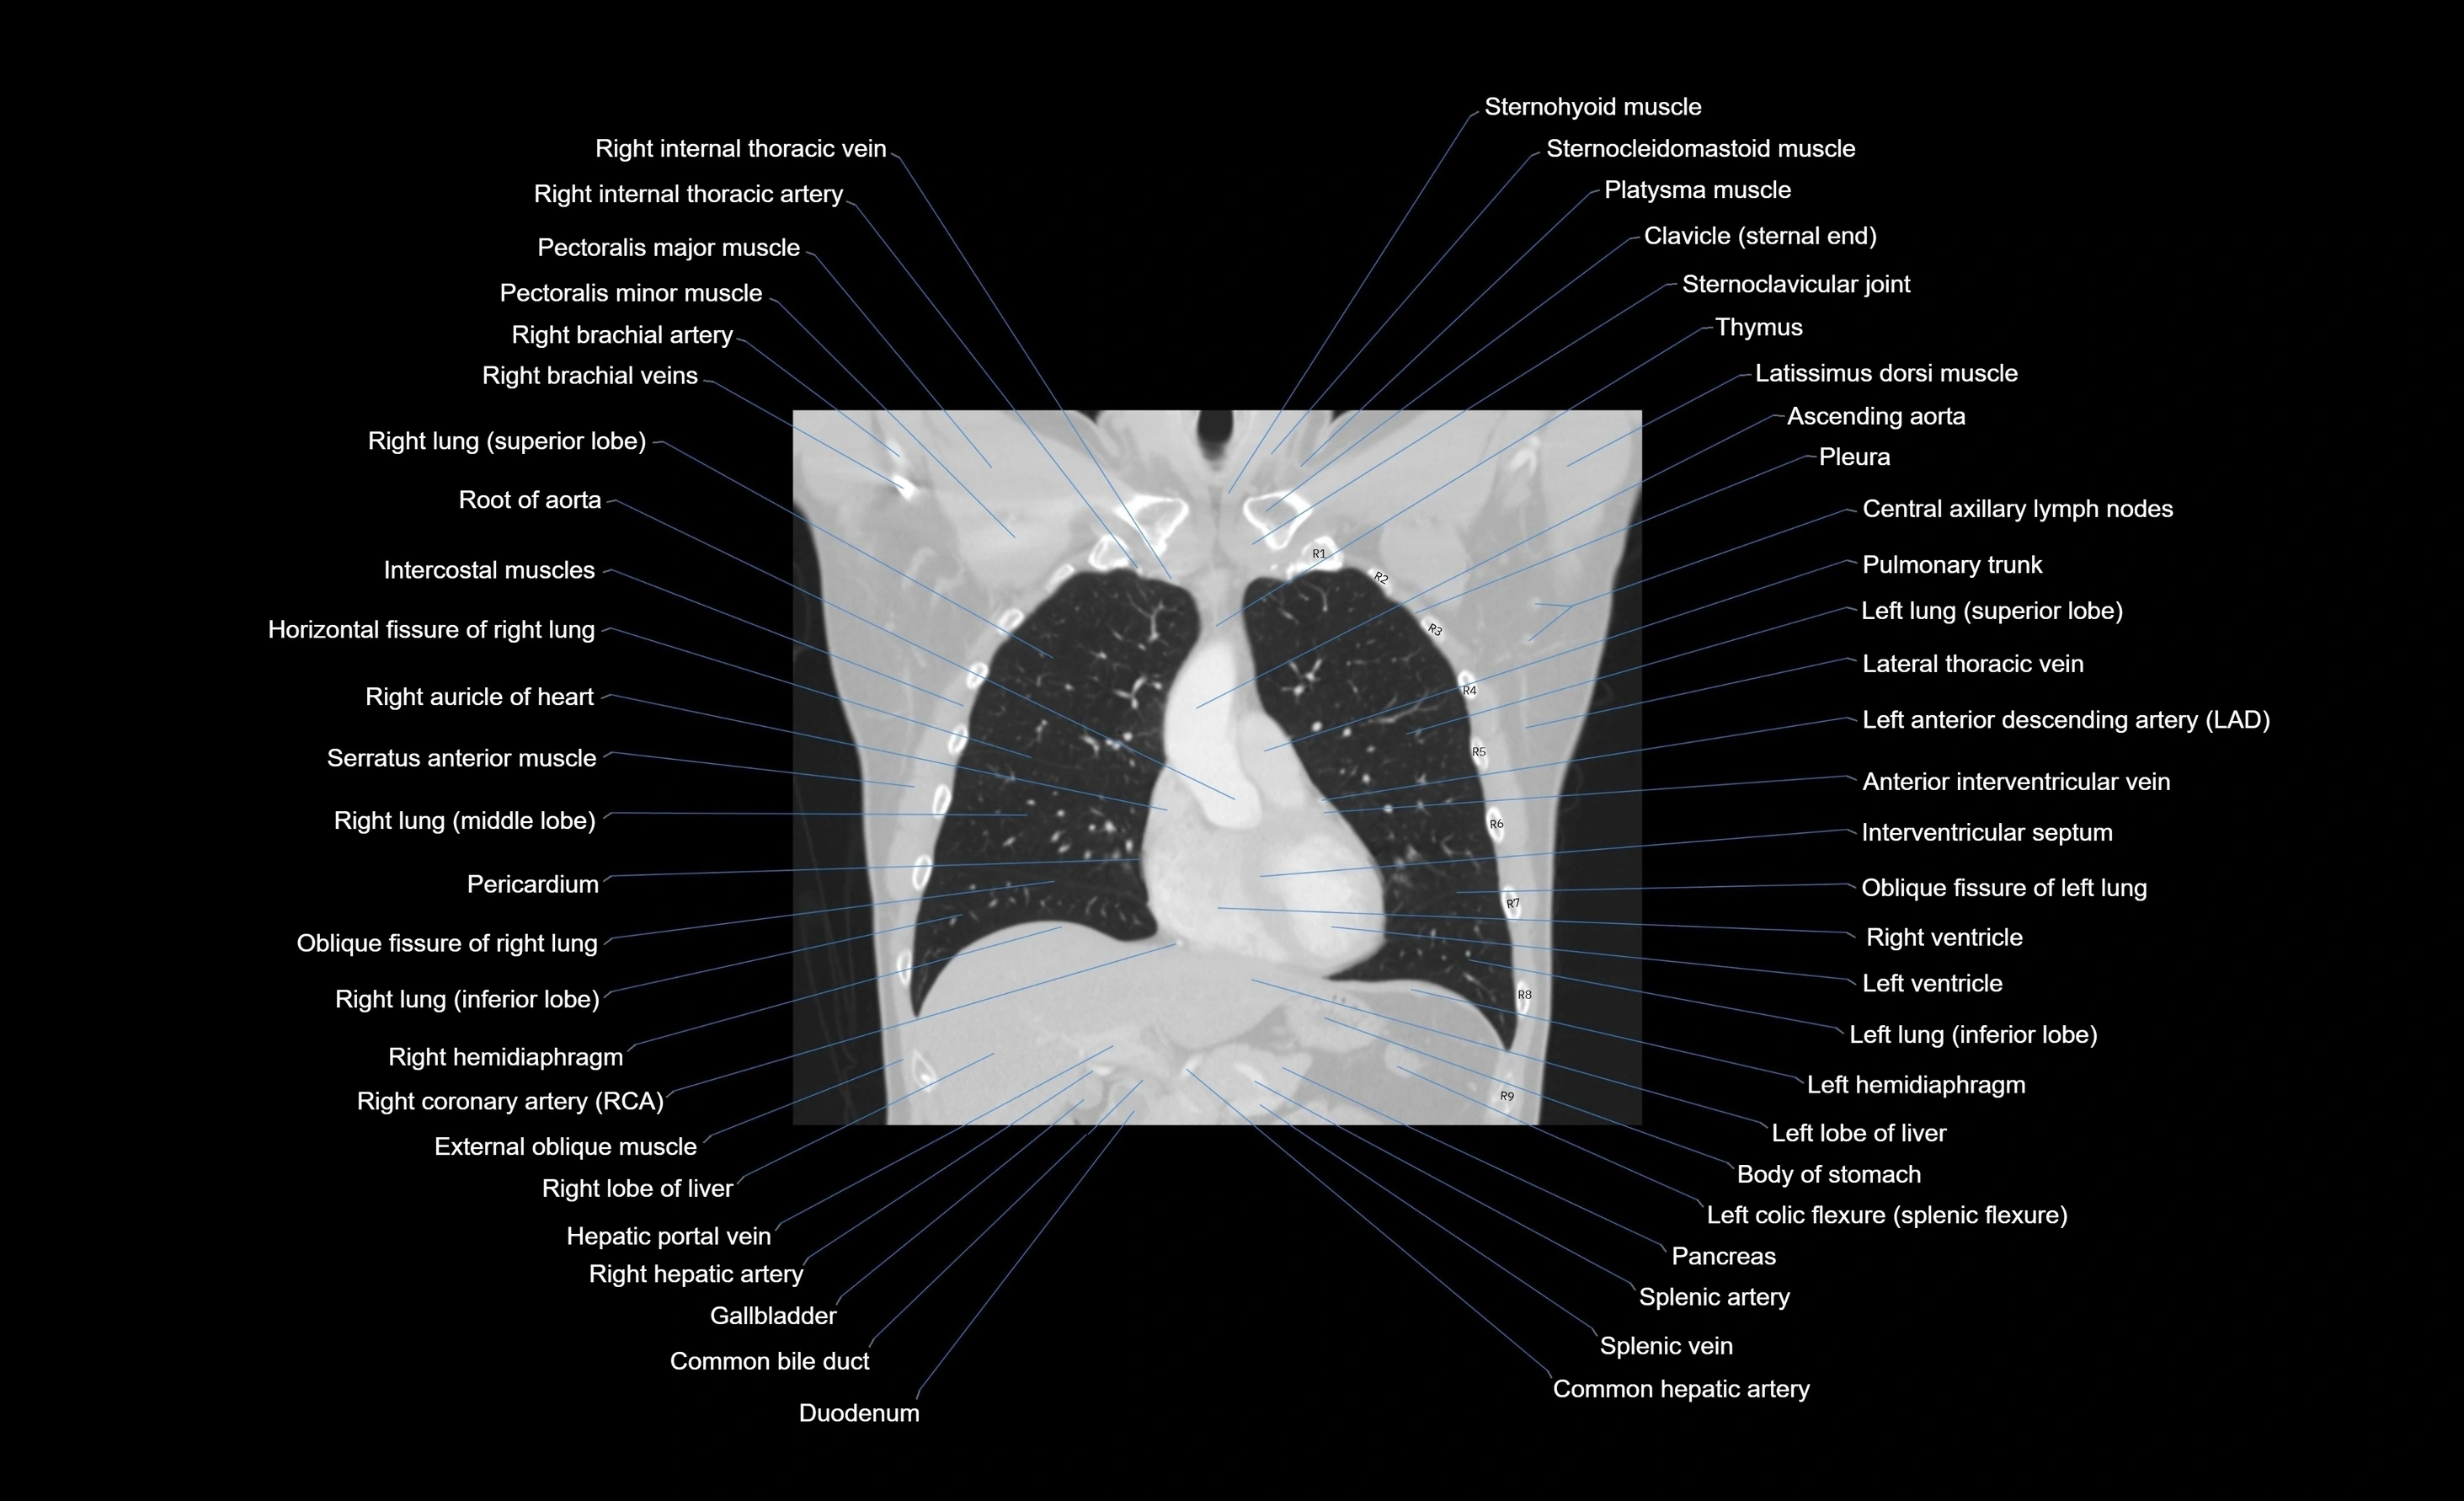

CT images